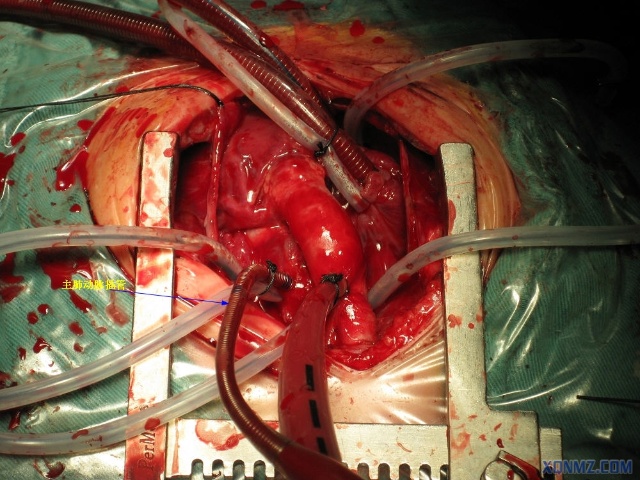

(二)大血管外科治疗:常规开展大血管外科开放性,包括高难度如Bentall+Sun氏;微创经股动脉切开主动脉人工覆膜支架血管腔内成形术,使主动脉夹层(A、B型)的急危重症患者得到有效治疗。